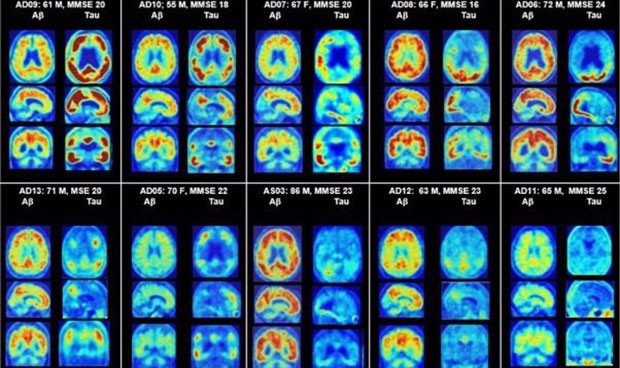

PET del cerebro que muestra placas amiloides y proteínas tau en alzhéimer. (Dean Wong, M.D., PH.D. y Ayon Nandi, M.S., PH.D.)